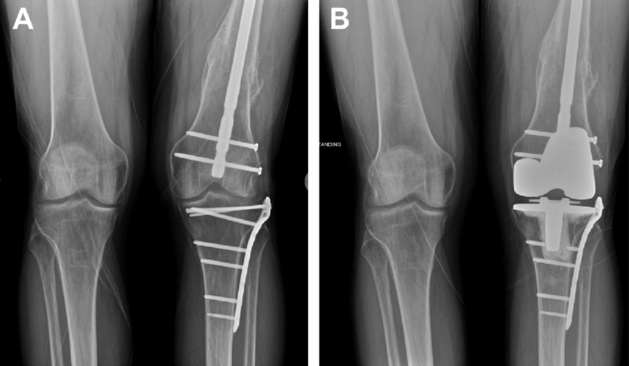

Complex Primary Knee Replacement—A challenging surgical scenario in case of previous knee surgeries with scarring and fibrosis making technical aspects more difficult. Old fractures of the shin or thigh bone resulting in malalignment which can compromise the Knee replacement and its soft tissue balancing-so crucial to a satisfactory outcome.